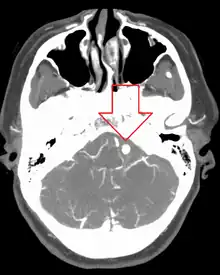

| Angiography of an aneurysm in a brain artery. The aneurysm is the large bulge in the center of the image. | |

Diagnosis of a ruptured cerebral aneurysm is commonly made by finding signs of subarachnoid hemorrhage on a computed tomography (CT) scan. If the CT scan is negative but a ruptured aneurysm is still suspected based on clinical findings, a lumbar puncture can be performed to detect blood in the cerebrospinal fluid. Computed tomography angiography (CTA) is an alternative to traditional angiography and can be performed without the need for arterial catheterization. This test combines a regular CT scan with a contrast dye injected into a vein. Once the dye is injected into a vein, it travels to the cerebral arteries, and images are created using a CT scan. These images show exactly how blood flows into the brain arteries.[38]